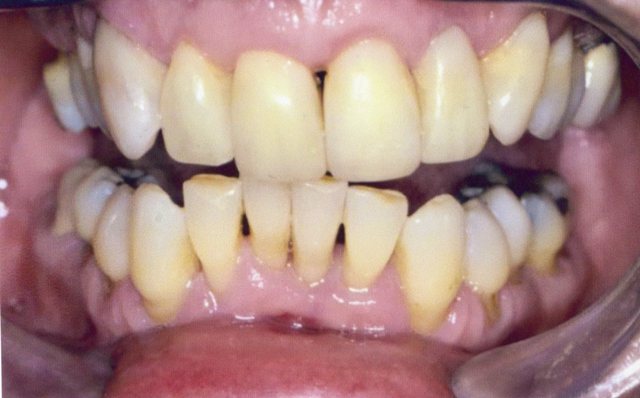

Περιστατικό 1 | Περιστατικό 2 | Περιστατικό 3 |

Περιστατικό 1 | Περιστατικό 2 |

Περιστατικό 3 | Περιστατικό 4 | Περιστατικό 5 |

Περιστατικό 1 | Περιστατικό 2 |

Περιστατικό 3 |

Περιστατικό 4 |

Περιστατικό 1 | Περιστατικό 2 | Περιστατικό 3 |

Περιστατικό 1 | Περιστατικό 2 |

Περιστατικό 3 | Περιστατικό 4 | Περιστατικό 5 |

Περιστατικό 1 | Περιστατικό 2 |

Περιστατικό 3 |

Περιστατικό 4 |